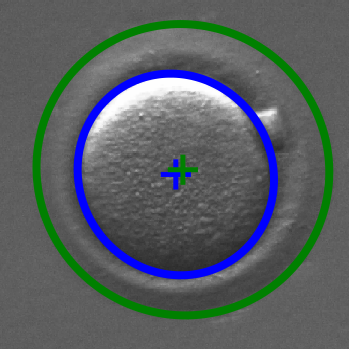

Infertility is becoming an issue for an increasing number of couples. The most common solution, in vitro fertilization, requires embryologists to carefully examine light microscopy images of human oocytes to determine their developmental potential. We propose an automatic system to improve the speed, repeatability, and accuracy of this process. We first localize individual oocytes and identify their principal components using CNN (U-Net) segmentation. Next, we calculate several descriptors based on geometry and texture. The final step is an SVM classifier. Both the segmentation and classification training is based on expert annotations. The presented approach leads to a classification accuracy of 70%.